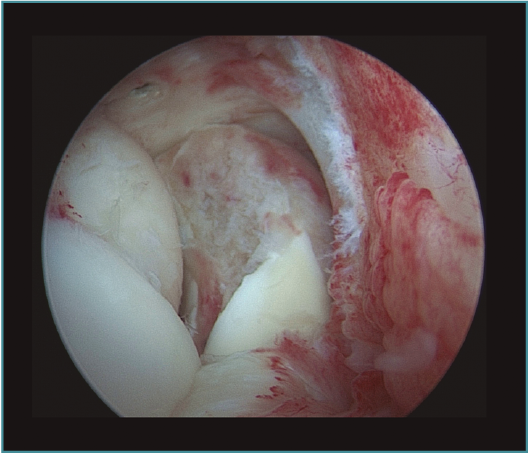

Seguidamente trabajaremos en la cámara posterior del codo, utilizando el portal transtricipital central como portal de visión y el portal posterolateral como portal de trabajo (estos portales van cambiando su función durante la cirugía y podemos añadir portales centrales y laterales más proximales, así como el portal lateral directo o soft spot)(20). No utilizamos el portal posteromedial para no poner en riesgo el nervio cubital, siguiendo las recomendaciones de Hilgersom, entre otros autores(18). En la parte posterior trabajaremos con el mismo orden: primero la resección de osteofitos en punta de olécranon, foseta olecraniana y parte lateral y medial del codo, así como extracción de cuerpos libres o tratamiento de lesiones osteocondrales en la parte posterior del cóndilo lateral del húmero (localización más frecuente), con desbridamiento del tejido inestable y/o perforaciones. Tras la parte ósea, realizaremos la capsulotomía posterior, para ganar flexión del codo (Vídeo, minutos 2:46-4:25; Figuras 9 a 14).

Figura 10. Caso 6. Visión artroscópica desde el portal anteromedial del engrosamiento y la hipervascularización de la cápsula anterior del codo, responsable del déficit de extensión.

Figura 11. Caso 6. Visión artroscópica desde el portal anteromedial de la extracción del fragmento osteocondral inestable de la cabeza del radio.

Figura 12. Caso 6. Visión artroscópica desde el portal anteromedial tras la resección del fragmento inestable. Se aprecia el engrosamiento y enrojecimiento de la cápsula anterior.